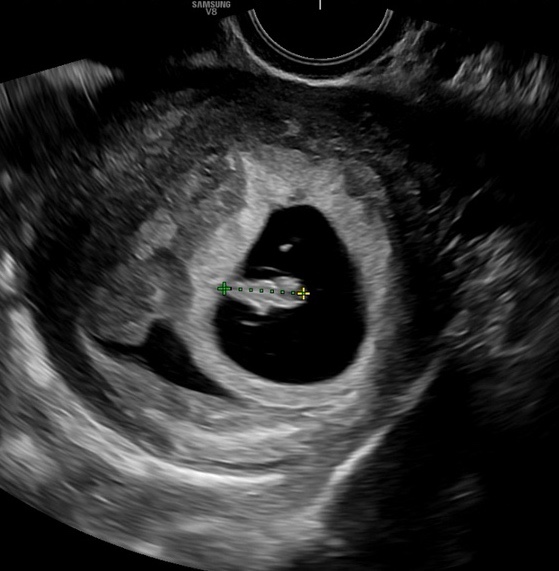

[임신초기] 9주차 진입 증상 :: 입덧 종류 (체덧, 먹덧, 양치덧 등), 두통과 잠의 싸움, 자궁 통증+다리저림

5주차에 극심한 입덧을 경험하고 난 후 그렇게 심한 입덧은 경험하지 못해서 6주차에 미식 거림을 거쳐 7주...

[임신초기] 임신 5주부터 8주까지 임신초기 증상은? 입덧하는 이유, 입덧에 도움되는 음식 추천

5주 1일차 되던 날 극심한 몸살과 두통 그리고 매쓰꺼움까지 더해져 임신을 알게된 날 입덧이라는 것을 처...